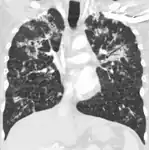

CT, showing extensive pulmonary parenchymal involvement consisting of irregular septal thickenings with ground-glass areas and centrilobular nodules with a peri-lymphatic distribution -

Miliary tuberculosis is a form of tuberculosis that is characterized by a wide dissemination into the human body and by the tiny size of the lesions (1–5 mm). Its name comes from a distinctive pattern seen on a chest radiograph of many tiny spots distributed throughout the lung fields with the appearance similar to millet seeds—thus the term "miliary" tuberculosis. Miliary TB may infect any number of organs, including the lungs, liver, and spleen.[5] Miliary tuberculosis is present in about 2 percent of all reported cases of tuberculosis and accounts for up to 20 percent of all extra-pulmonary tuberculosis cases.[6]

Testing for miliary tuberculosis is conducted in a similar manner as for other forms of tuberculosis, although a number of tests must be conducted on a patient to confirm diagnosis.[7] Tests include chest x-ray, sputum culture, bronchoscopy, biopsy, CT/MRI, blood cultures, fundoscopy, and electrocardiography.[1] The tuberculosis (TB) blood test, also called an Interferon Gamma Release Assay or IGRA, is a way to diagnose latent TB.A variety of neurological complications have been noted in miliary tuberculosis patients—tuberculous meningitis and cerebral tuberculomas being the most frequent. However, a majority of patients improve following antituberculous treatment. Rarely lymphangitic spread of lung cancer could mimic miliary pattern of tuberculosis on regular chest X-ray. [14][4]